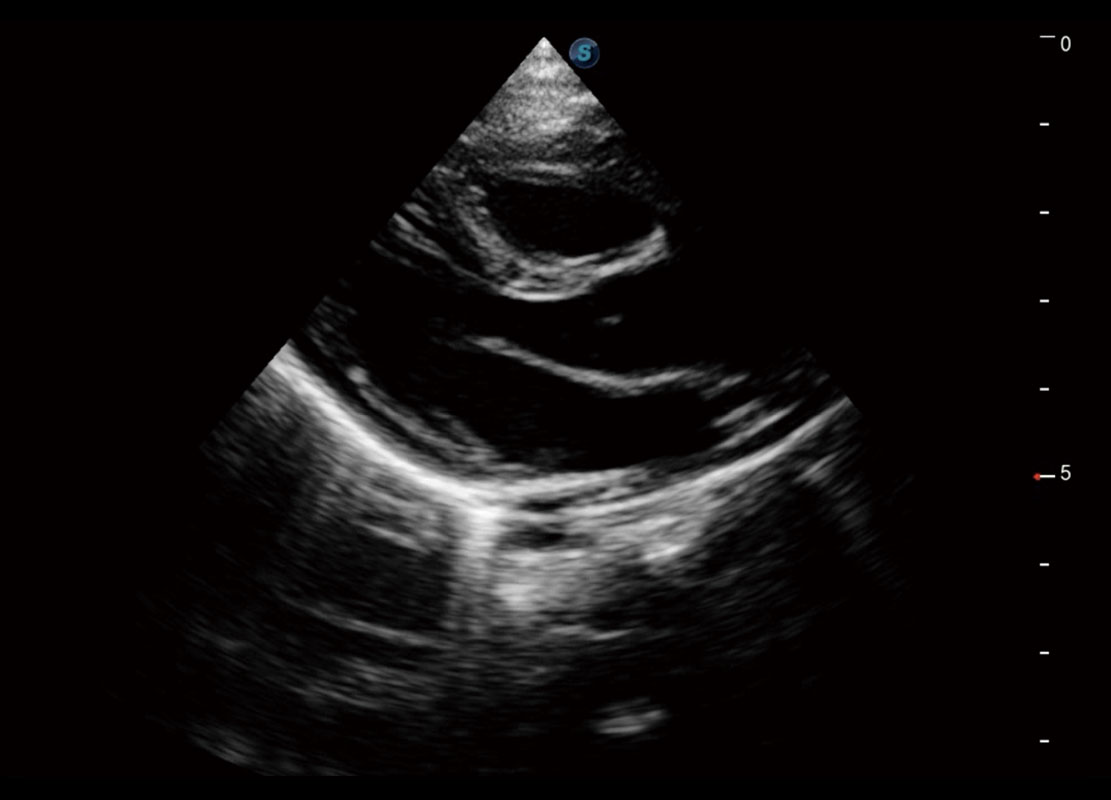

胎心筛查

P60搭载一系列胎儿心脏成像技术,实现精细的胎儿心脏评估。

• 四腔切面

• 四腔心血流

• 右室双出口

• 胎心容积成像